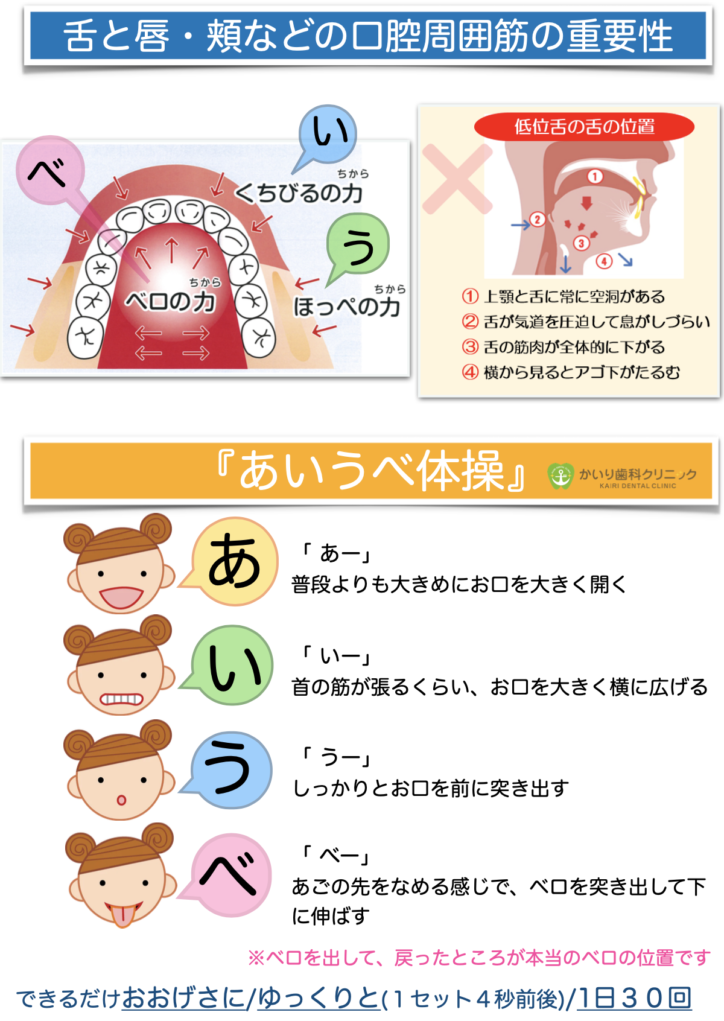

子どもの歯並び予防のMFT②〜舌の動きと口呼吸改善トレーニング(あいうべ体操)〜

2024.06.13

あいうべ体操

口呼吸の改善に役立つだけでなく、全身の免疫力を上げることにもつながる効果もある『あいうべ体操』のご紹介

あいうべ体操(考案者の今井一彰先生のYouTube動画はこちら)

福岡の『みらいクリニック』の内科医である今井一彰先生が考案なさった体操です。

口呼吸を鼻呼吸に改善していく簡単な口の体操で、一日30回を目安に続けることで舌力がついて自然を口を閉じることができるようになると言われています。

大切なポイント

『ベー』のときにあごの先を舐める感じでおもいっきり舌を突き出して伸ばすことが大切です!

その後、ゆっくりお口を閉じた時の舌の位置が舌の正しい置き場所である『スポットポジション』です☆

子どもの歯並び予防の考え方(15)〜口呼吸のリスクと改善トレーニング(あいうべ体操)〜

2024.06.06

特に『お口ポカン・口呼吸』は以下のように様々な病気の重症化につながるリスクがあります。

お口を開いていることで虫歯や歯肉炎や歯並びなどのお口の問題だけでなく、アレルギーやアデノイドの肥大など様々な疾患を重症化させるリスクとなります。

つまり、お口をきちんと閉じるようにできるようになれば、口呼吸、鼻へい、気道閉塞、アレルギーなどを軽症化できる可能性もございます。

当院では、口呼吸の改善に役立つだけでなく、全身の免疫力を上げることにもつながる効果もある『あいうべ体操』の普及に力を入れております。

あいうべ体操(考案者の今井一彰先生のYouTube動画はこちら)

福岡の『みらいクリニック』の内科医である今井一彰先生が考案なさった体操です。

口呼吸を鼻呼吸に改善していく簡単な口の体操で、一日30回を目安に続けることで舌力がついて自然を口を閉じることができるようになると言われています。